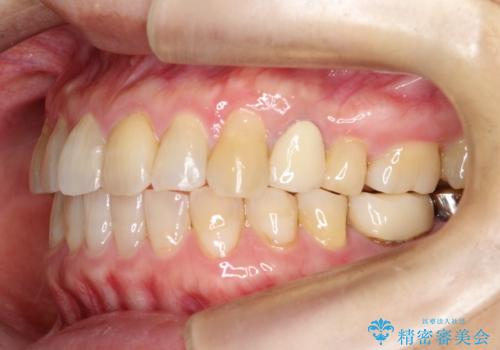

【インビザライン】前歯のガタガタを治したい

- 前歯のガタガタを主訴に来院されました。

上の歯の前突も気になってたため、奥歯の遠心移動も行いながらインビザラインにて治療を行いました。

前歯も下がり満足していただきました。

今回は奥歯の遠心移動とIPRを行って配列しています。